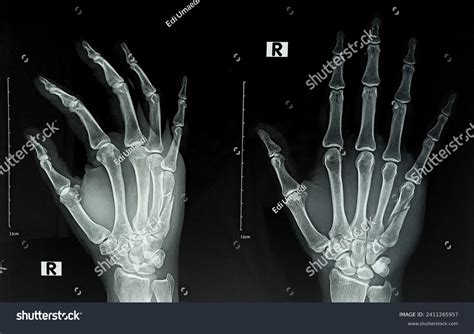

A broken hand x-ray is a type of medical imaging that uses low levels of radiation to produce images of the bones in the hand. These images are crucial for diagnosing fractures, dislocations, and other bone-related injuries. The x-ray machine emits X-rays that pass through the body and are absorbed differently by various tissues. Bones, being denser, absorb more X-rays and appear white on the resulting image, while softer tissues appear darker.

• Positioning: You will be asked to place your hand in a specific position on the x-ray table. The technician will ensure that the hand is properly aligned to get the best possible images.

• Imaging: The x-ray machine will be positioned over your hand, and you will be asked to remain still while the images are taken. The process is quick and usually takes only a few minutes.